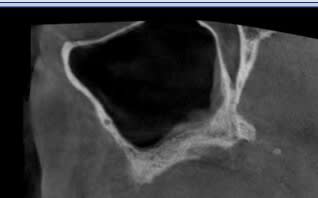

en voilà un autre; question:

comment gérer la découpe du volet osseux avec une artère volumineuse intra-osseuse sans provoquer d'hémorragie ?

ci joints quelques clichés.

elle a l'air grosse .... !!!!

dissection de la fenêtre autour de l'artère (piezo).

mais je ne voudrais pas avoir le faire...!

Ou un implant plus court?

Sinuslift interne?

si tu veux éviter hémorragie, faut la mettre en évidence l'électrocoaguler ou éventuellement ligaturer mais la première solution est la plus simple.

normalement tu la vois par transparence quand tu fais to volet osseux.

la piézzo permet un certain confort pour libérer l'os autour

tu passes dessous

T'as une pano, car les coupes dont pas super explicite

cet image est réalisée avec quel type de cone beam ??